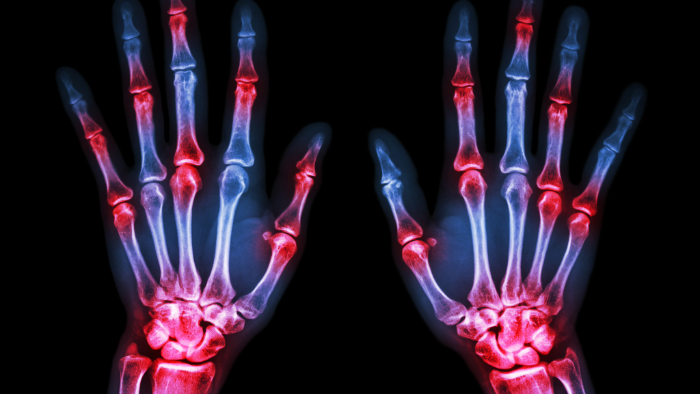

x-ray of two hands with red spots over the joints indicating arthritis

At its core, arthritis is a term that simply means inflammation of the joints, but that definition doesn’t quite capture how complex or varied it really is. There are over 100 different types of arthritis, each with its own triggers, symptoms, and long-term consequences. (12) Some forms are purely mechanical, while others are driven by immune dysfunction. Some come on slowly and quietly over the years, and others seem to appear overnight. What they all have in common is this, they compromise your joints.

Here’s how arthritis shows up in most people (13, 14):

• Joint pain and stiffness, especially after periods of rest due to decreased lubrication

• Swelling or warmth around the joints

• Reduced range of motion or joint deformities

• Difficulty with movement, walking, or daily tasks

• In more aggressive types, fatigue and systemic inflammation